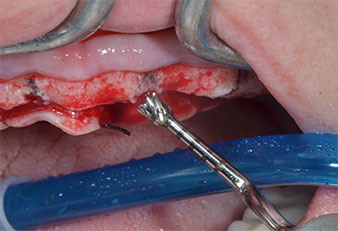

A flame-shaped, diamond-coated piezoelectric instrument (Piezomed I1) was used to mark the implant positions and to perform pilot preparation (Fig. 3). Care was taken to use an up and down movement, with reduced power, full irrigation and low pressure (below 300 g). Next a pilot instrument (Piezomed I2A/I2P) was applied for the initial 2 mm diameter enlargement of the implant sites (Fig. 4), followed by a 3 mm insert (Fig. 5).

In case of dense bone the whole instrument sequence including the intermediate instruments Piezomed Z25P and Z35P should be used to widen the osteotomies before the next enlargement step.

They are also indicated for preparation near the sinus membrane in connection with internal augmentation procedures or when there is less than 4 mm of residual bone height.

In the present case the Z25P and Z35P instruments were not used due to the relatively soft posterior bone, which was easily managed with the I3A/I3P.